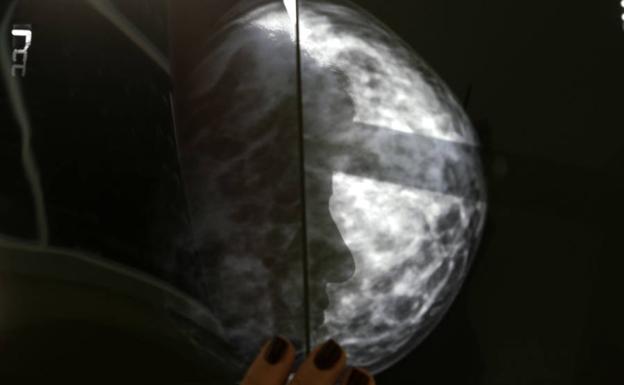

Los investigadores aislaron y reactivaron células T específicas del cáncer de una sola paciente cuyo tumor de mama estaba en estado de metástasis y las células reactivadas eliminaron todas las lesiones